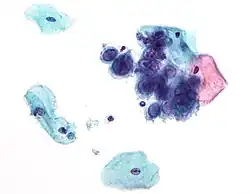

Micrograph of a normal pap smear

Micrograph of a Pap test showing a low-grade intraepithelial lesion (LSIL) and benign endocervical mucosa. Pap stain.